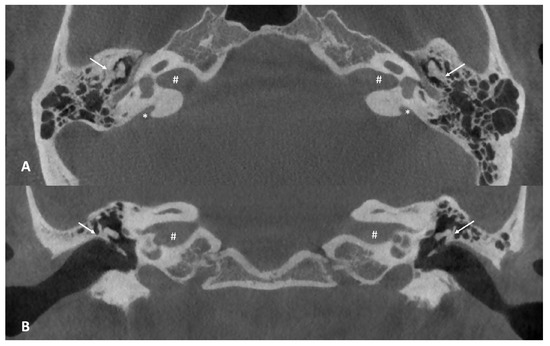

At this point, the patient was referred to our center to obtain a second opinion, given the unsatisfactory hearing improvement after surgery. A cone beam computed tomography (CBCT) of the temporal bone was performed, revealing bilateral enlarged vestibular aqueducts (EVAs) associated with a malformation of the ossicular chain, which appeared bilaterally fixed to the upper lateral wall of the middle ear (Figure 2). The vestibular aqueduct diameter at the midpoint resulted to be 1.74 mm on the right and 2.45 mm on the left.

Figure 2. (A) Axial cone beam CT scan of the temporal bone. Note the abnormal anatomy of the middle ear, with the ossicular chain almost “fused” with the lateral wall of the tympanic cavity (white arrows) and the enlarged vestibular aqueduct on both sides (white asterisks), 1.74 mm on the right and 2.45 mm on the left. (B) Coronal cone beam CT scan of the temporal bone. Note the fusion of the incus to the lateral wall of the tympanic cavity (white arrows). The white hash (#) found in both axial and coronal images, identifies the internal auditory canal.